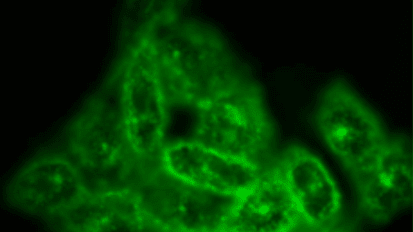

Imaging Technique Examines Uterine Electrophysiology in Preterm Contractions